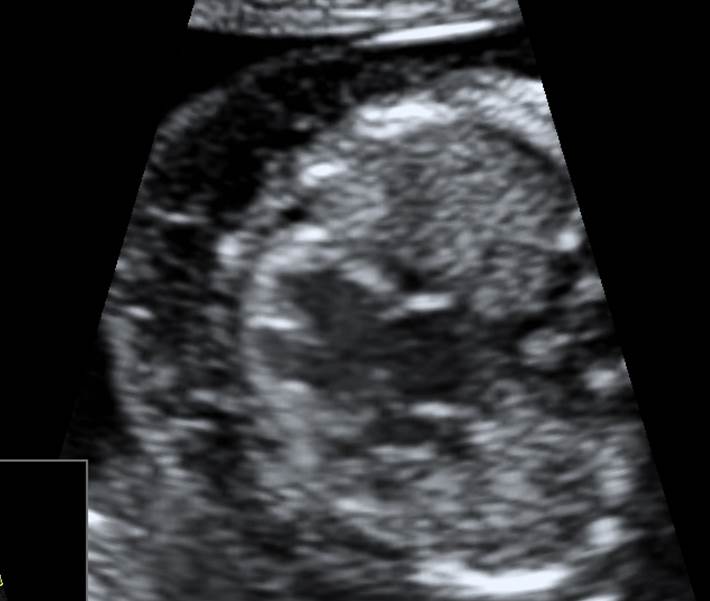

Вопрос 11

Поставьте диагноз

• А — норма;​

• Б — АВ-канал ;​

• В — транспозиция магистральных сосудов;

• Г — гипоплазия левого желудочка

Ответ на вопрос 11